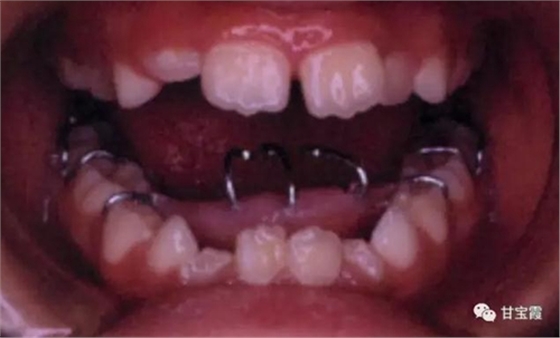

家長(zhǎng)發(fā)現(xiàn)孩子嘴型不好看,吃東西也咬不斷,就帶著孩子找我看診,經(jīng)過(guò)檢查和診斷,我決定給孩子戴個(gè)舌刺,讓孩子的舌頭舔不著下前牙,如下圖

一個(gè)半月后復(fù)診檢查發(fā)現(xiàn)前牙反頜和開(kāi)合都有所好轉(zhuǎn)